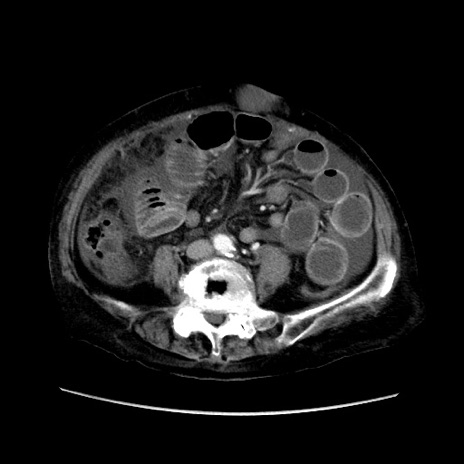

冠状断像